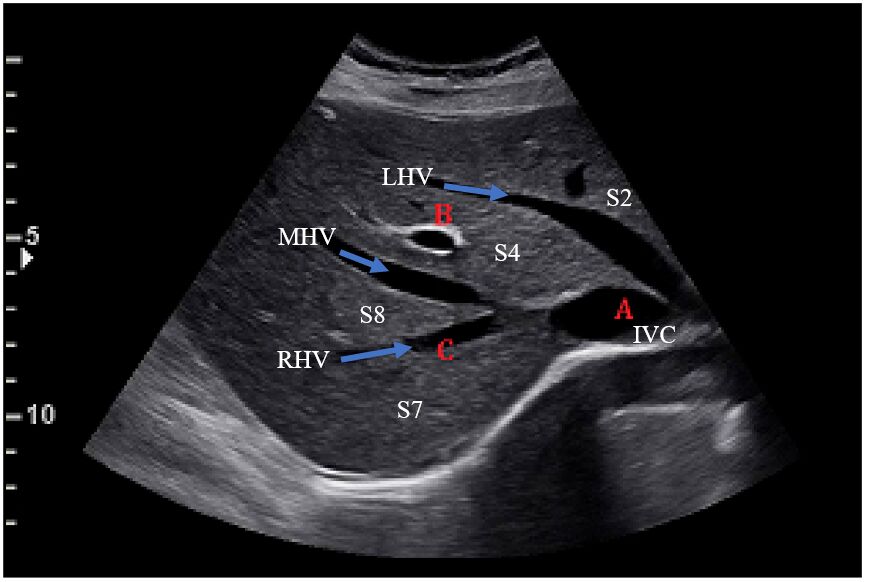

66.下圖為肋骨弓下緣之超音波掃描影像,其編號A、B、C的解剖位置,依序應為下列何者?

三叉是由三條肝靜脈:右肝靜脈RHV、中肝靜脈MHV、左肝靜脈LHV組成,這三條肝靜脈離開肝臟注入下腔靜脈(IVC)。RHV、MHV、LHV由右至左將肝臟分成6葉:S7、S8、S4、S2。

編號A指的是下腔靜脈(IVC)

編號B指的是肝門靜脈,肝門靜脈的血管壁有更亮白的回音,肝靜脈的血管壁比較低回音,因此B所指的是門靜脈

編號C指的是右肝靜脈(RHV)

對應的選項為 (C) 下腔靜脈、門靜脈、右肝靜脈

從下圖也可以明顯看出肝門靜脈(PV)的血管壁比肝靜脈(HV)、下腔靜脈(IVC)亮